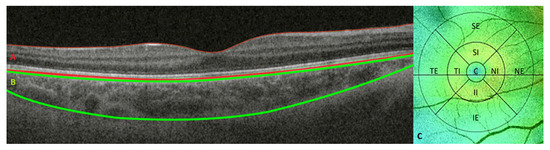

3.1. Retinal and Choroidal Thickness Assessment